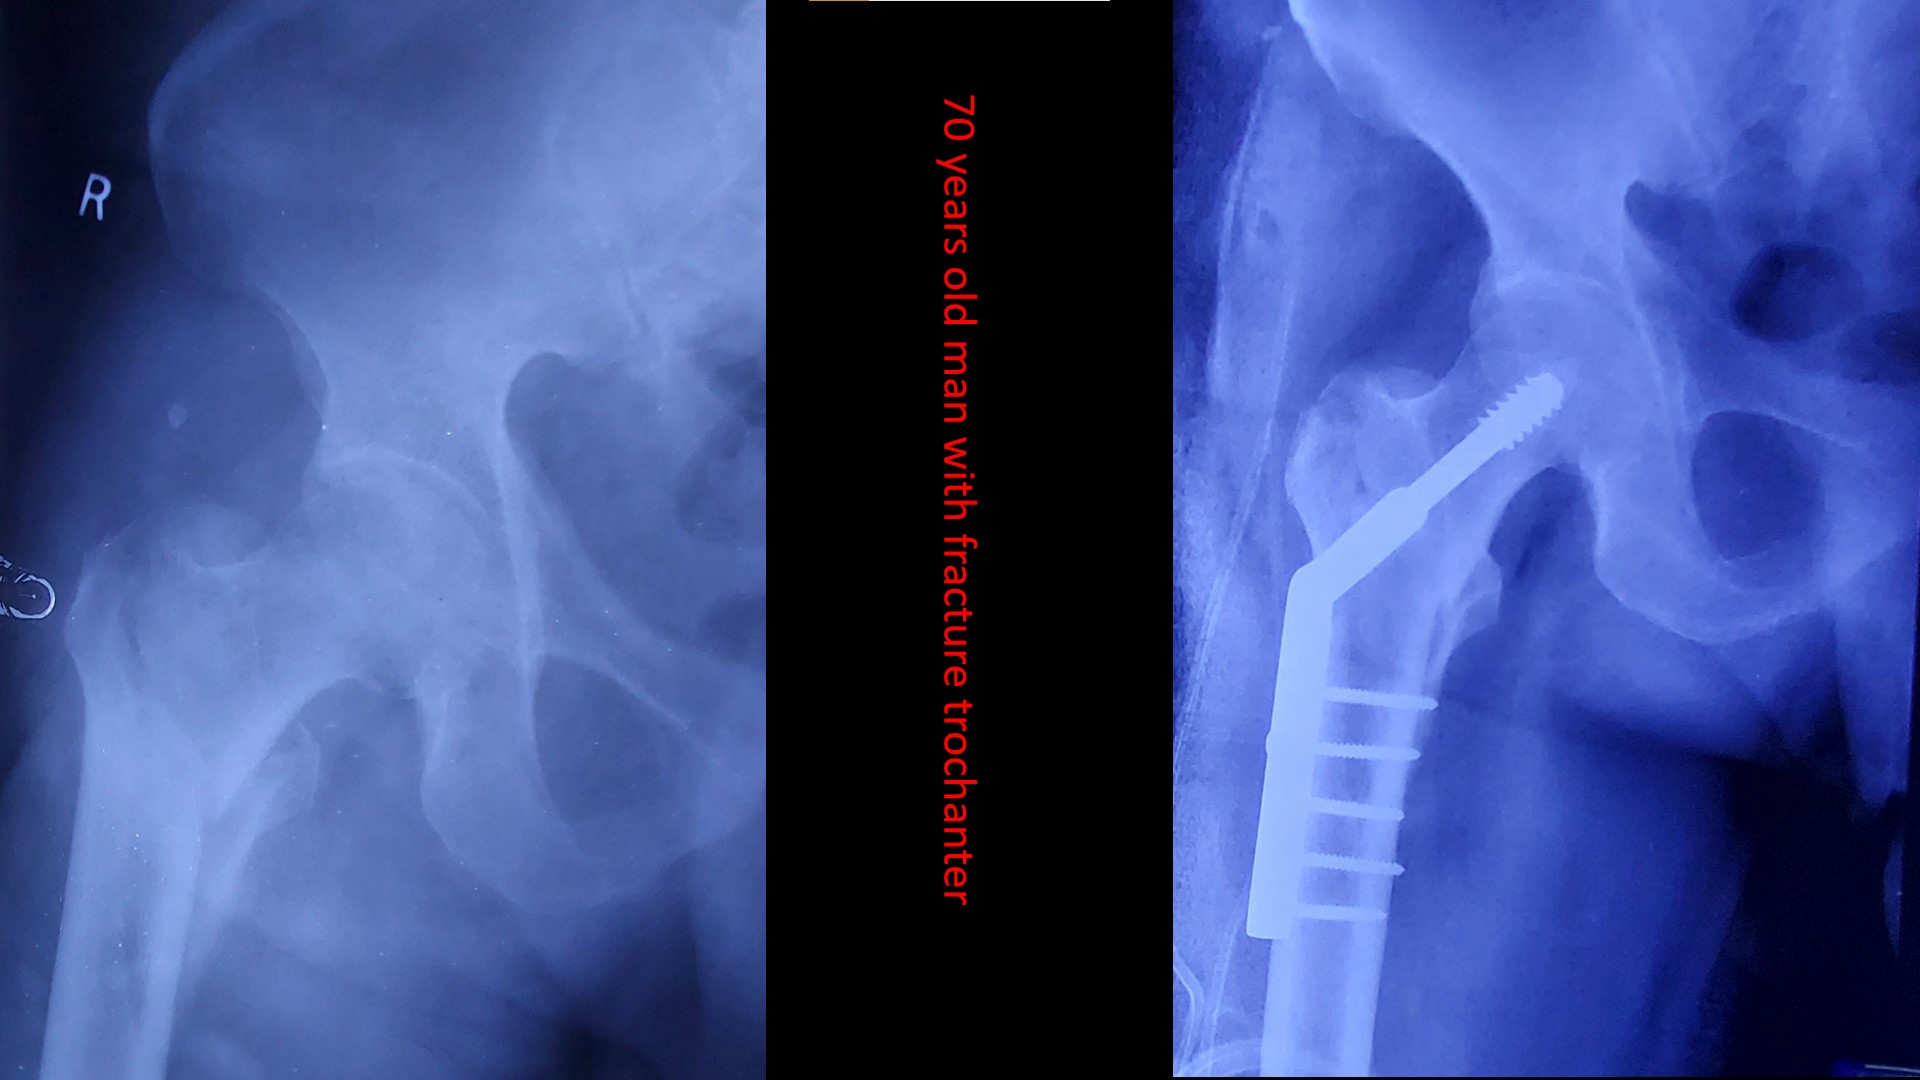

The care you deserve.

Please send us a message, or call us for an appointment. +919287283131,+9188166438,04662223131, 04662223785